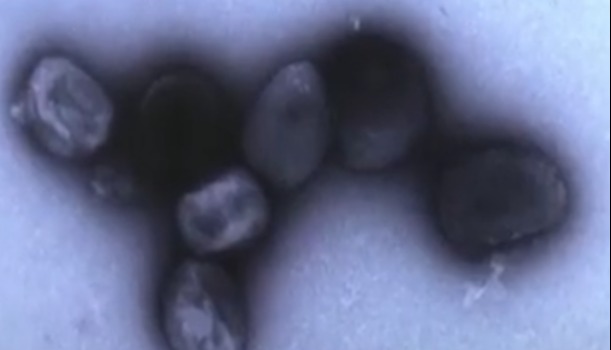

香港中通社9月16日電 據重慶衛健委網站通報,9月16日,重慶市確診1例境外輸入猴痘病例。

該病例為自國外中轉重慶入境人員,在按規定進行入境人員新冠肺炎疫情防控集中隔離期間,發現皮疹等症狀,經重慶市疾控中心實驗室檢測及中國疾控中心復核,實驗室結果猴痘病毒核酸陽性,國家組織專家診斷為猴痘確診病例。患者正在定點醫院進行集中隔離治療,情況穩定,其密切接觸者均已落實隔離醫學觀察措施。 通報稱,重慶方面高度重視猴痘病例的處置工作,第一時間指揮調度、安排部署。市衛生健康委積極行動、迅速響應,深入開展流行病學調查,加強追蹤排查、核酸檢測、醫療救治和全面消殺等相關工作。經專家研判,該病例入境重慶即被隔離管控,無社會面活動軌跡,疫情傳播風險低。 中國疾控中心病毒學首席專家董小平8月10日在新聞發佈會上表示,猴痘是一種由猴痘病毒感染所致的人獸共患病毒性疾病,臨床上主要表現為發熱、皮疹、淋巴結腫大。今年5月以來,已在全球70多個國家和地區傳播。 董小平稱,今年6月,國家衛生健康委與國家中醫藥局聯合印發了《猴痘診療指南(2022年版)》,對各地做好猴痘的診療工作提供了指引。下一步,將繼續進一步加強猴痘的防控工作。(完) 【編輯:丘志彬】